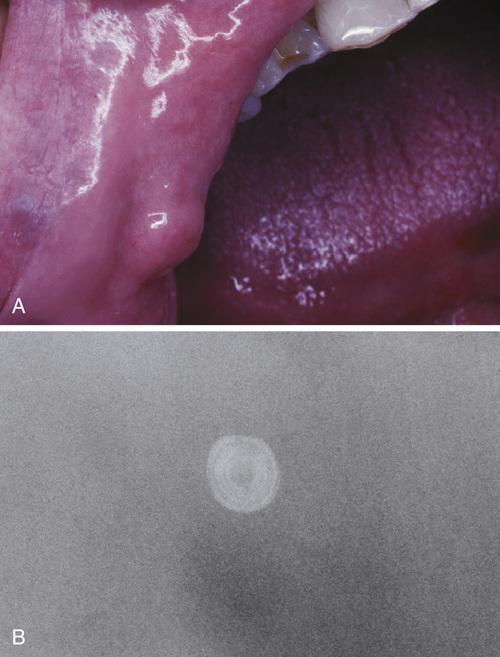

Hard mass at the orifice of Wharton duct. The long, tortuous, upward path of this duct and its thicker, mucoid secretions may be responsible for this finding.

sialolith

- A mass of a minor gland presenting as a hard nodule in the upper lip.

- A soft tissue radiograph revealed a laminated calcified mass.

sialolith